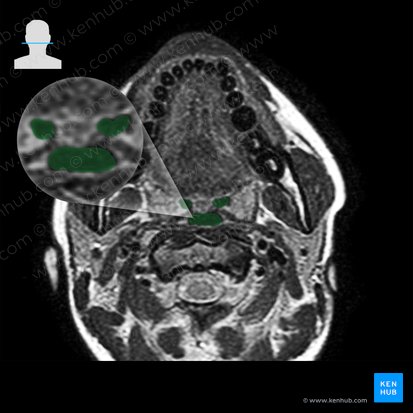

Orofaringe

La orofaringe o la porción oral de la faringe, se extiende desde el paladar blando hasta el borde superior de la epiglotis y tiene cuatro paredes (una anterior, dos laterales y otra posterior). Su pared anterior se define por la cara faríngea de la lengua. Cuando la base de la lengua está deprimida (por ejemplo durante un examen clínico) la pared anterior es visible a través del orificio denominado istmo de las fauces. Este orificio está limitado por el arco palatogloso.

Las paredes laterales de la orofaringe presentan reparos relacionados con los arcos palatofaríngeos y las tonsilas palatinas (amígdalas palatinas). La pared posterior de la orofaringe se extiende desde el cuerpo de la segunda hasta la porción cervical de la tercera vértebra cervical (C2-C3).

Ubicación C2-C3; entre la nasofaringe y la laringofaringe